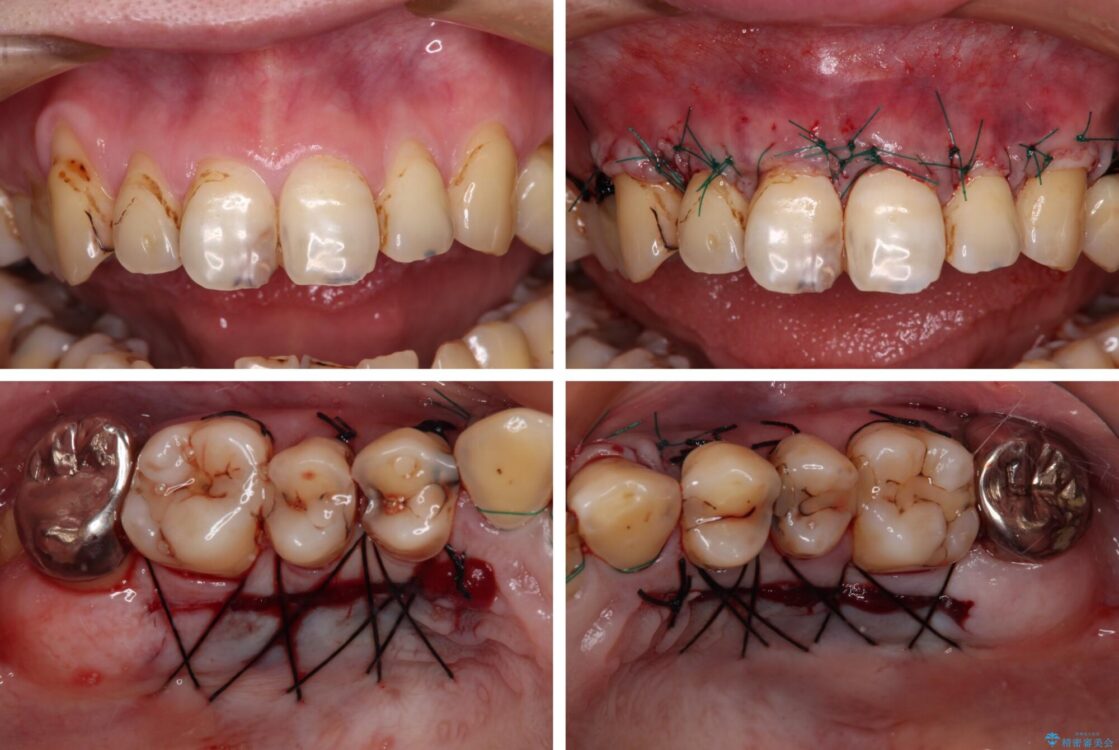

治療途中

• むし歯だらけの前歯をオールセラミッククラウンできれいに 治療途中画像

全顎的にむし歯が多く、根管治療の必要な奥歯や、審美的に気になっている前歯を中心にオールセラミッククラウンにて補綴治療を行うこととしました。

上顎前歯は歯肉退縮により歯根が露出していたため、事前に歯肉移植術により根面被覆を行い、その後にオールセラミッククラウンを装着することとしました。